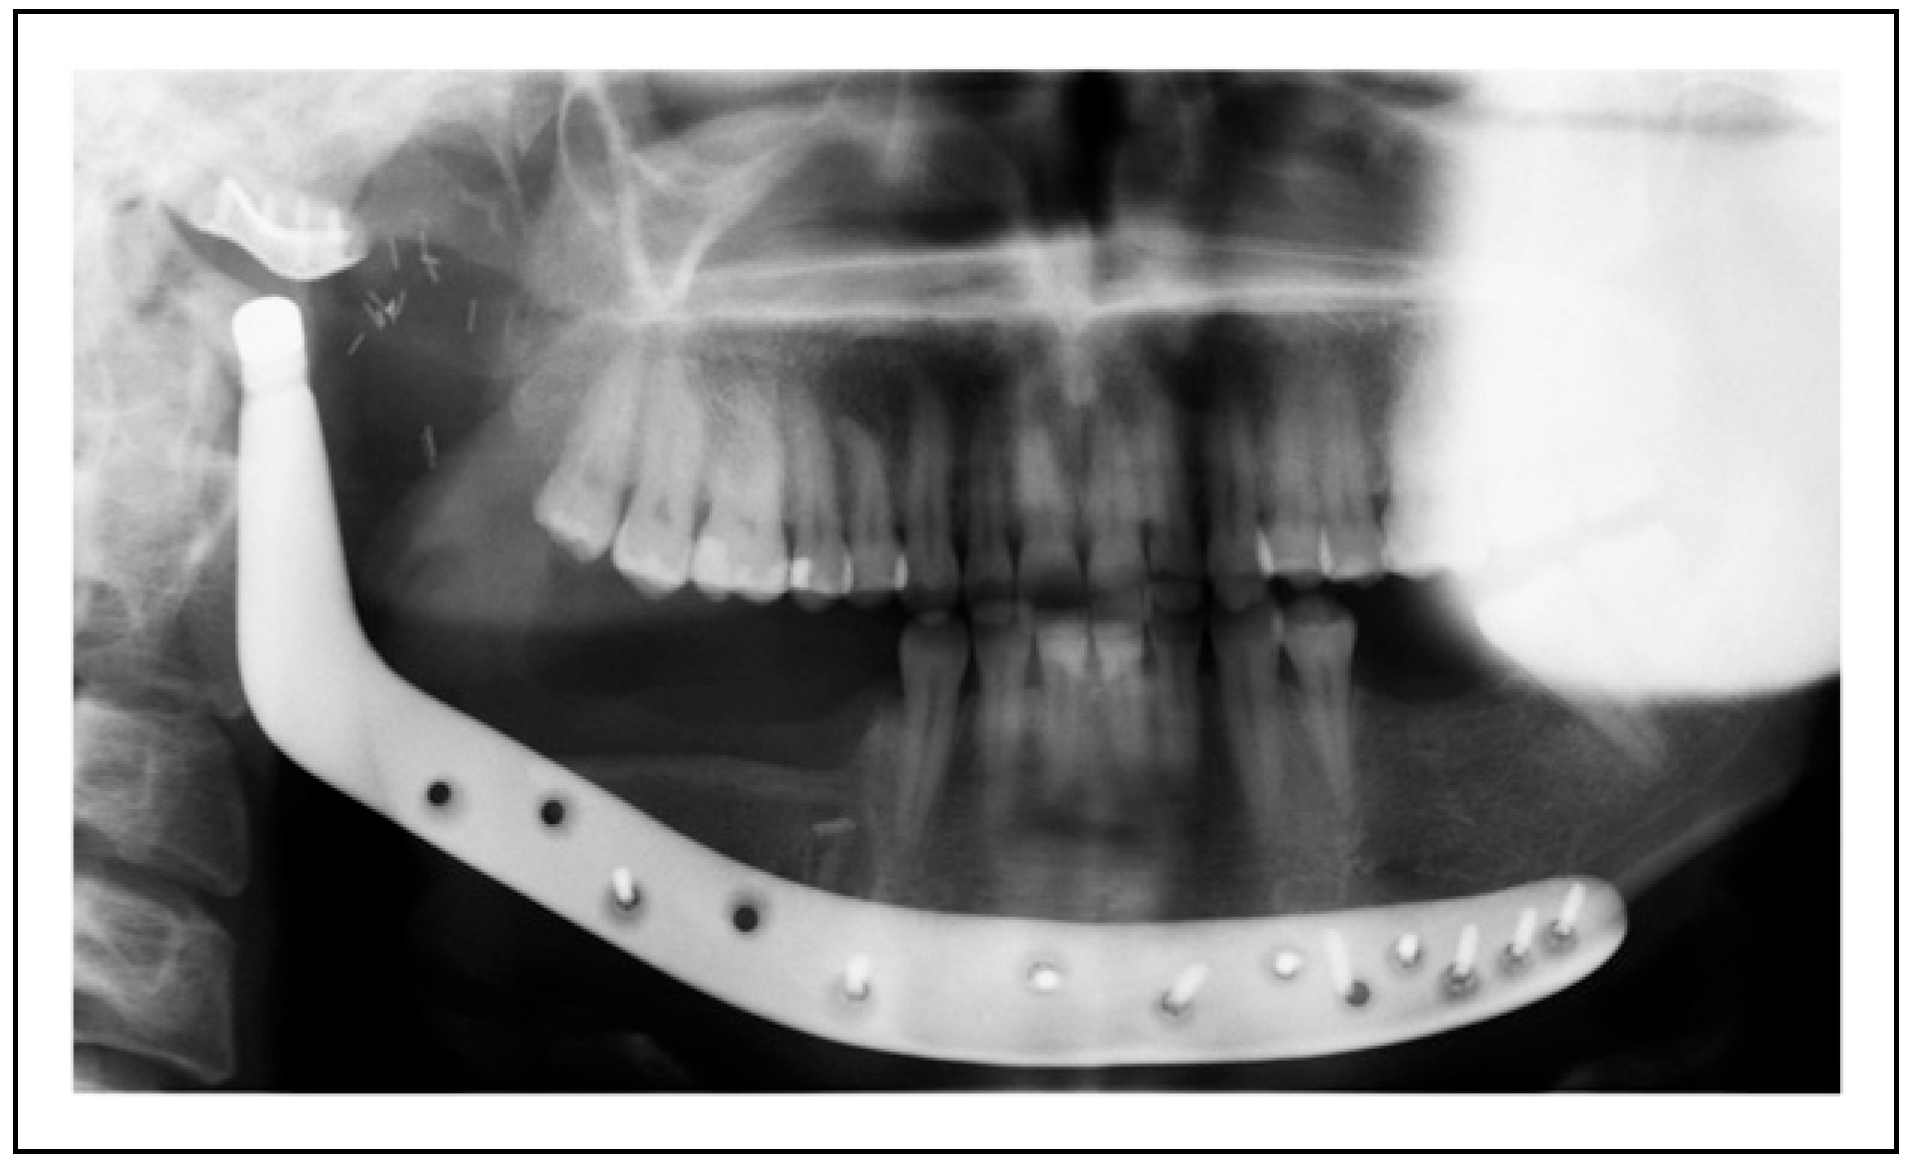

Two-Stage Regime, Patient 1